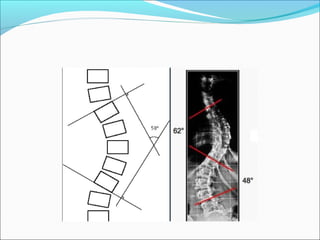

Cobb metodu

Eğriliğin derecesinin belirlenmesinde standart ölçüm

yöntemidir.

Sefalik end vertebranın üst, kaudal end vertebranın

alt yüzeyleri eğrilikte en fazla eğime sahiptirler.

Üst uç vertebranın üst kenarı ve alt uçtaki

vertebranın alt kenarına paralel olarak uzatılan

çizgiler arasındaki açı “c” Cobb açısıdır.